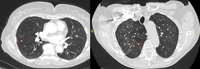

Computed tomography (CT) sections from two cases with benign perifissural nodules. Note the smooth margins and the normal undisturbed adjacent fissure

From the collection of Dr George Tsaknis, MD, PhD, FRCP(London), MRQA, MAcadMEd, PGCert; used with permission